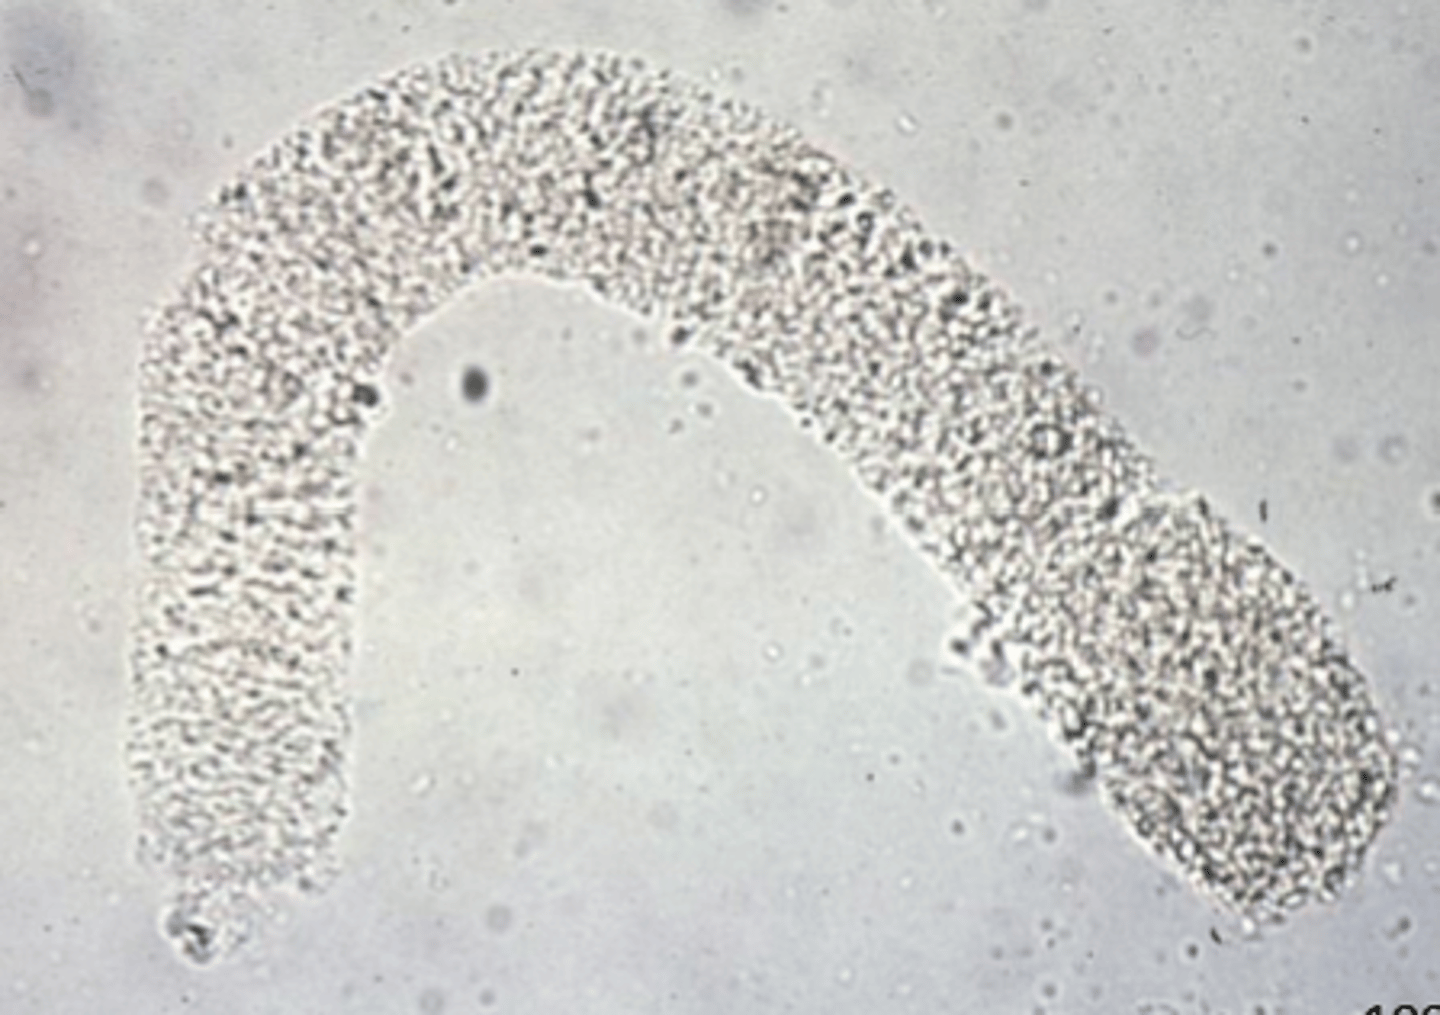

microfilaria

urine

microfilaria